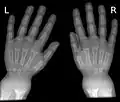

Renflement visible au niveau du poignet.

Les épiphyses sont l'objet d'un remodelage (le tissu osseux non minéralisé s'accumule de façon anarchique) aboutissant à un élargissement des extrémités des os : bourrelets ou nodosités osseuses visibles ou palpables notamment au niveau des côtes, des poignets ou des chevilles.

Les atteintes des membres sont les plus caractéristiques. Les bourrelets ou renflements osseux sont d'abord palpables au poignet, bord externe du radius (précoce), et à la cheville (au-dessus de la pointe de la malléole externe), puis visibles.

La radiologie confirme le diagnostic, et il est inutile de les multiplier. Le défaut de minéralisation des os longs s'observe particulièrement sur les radiographies de face d'un poignet et des genoux : retard ou irrégularités des points d'ossifications attendus pour l'âge (maturation squelettique), lignes métaphysaires irrégulières donnant un aspect « en toit de pagode », la corticale de la diaphyse est amincie, la densité osseuse est diminuée donnant un aspect vermoulu. Les os longs s'incurvent.